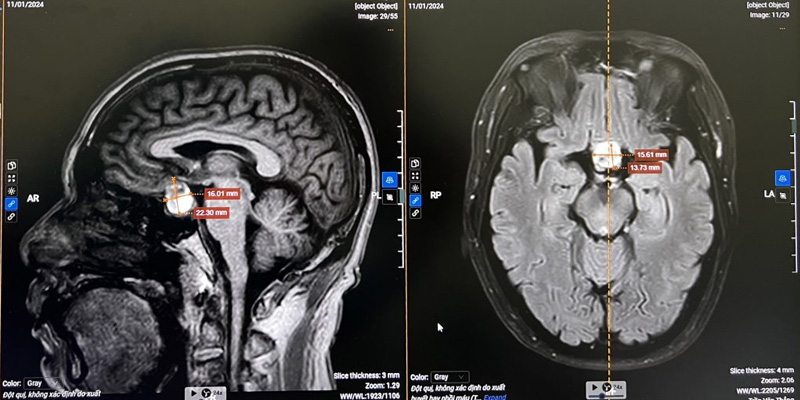

Hình ảnh học

- MRI (Cộng hưởng từ): Là tiêu chuẩn vàng để phát hiện khối u, xác định kích thước, vị trí và mức độ xâm lấn.

Chẩn đoán ung thư não bằng MRI